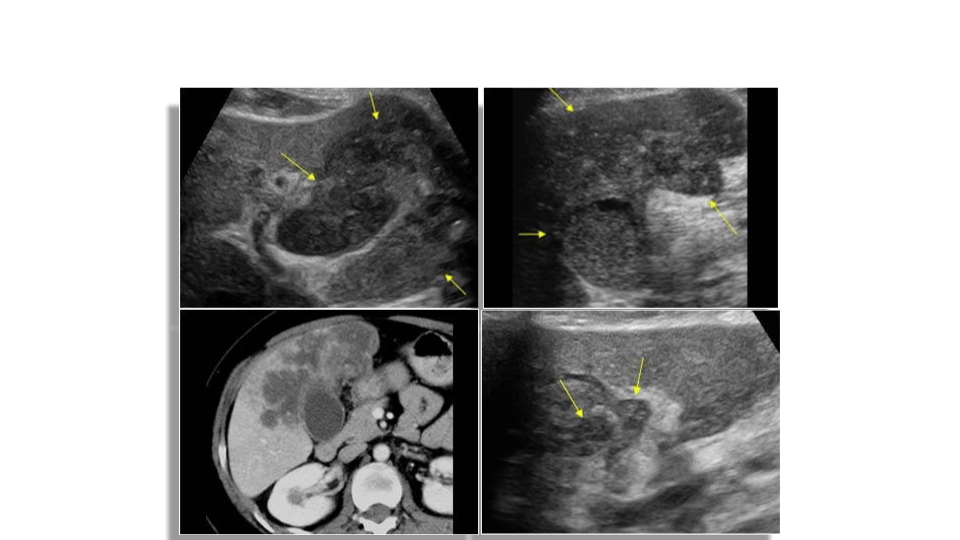

Caroli’s disease

Rare congenital disease of the intrahepatic biliary tree which leads to non obstructive saccular or fusiform (less common) dilatation of the intrahepatic bile ducts. There’s 2 types

Bile duct dilatation can lead to stasis of bile and sludge/stone formation. There is a predisposition to develop ascending cholangitis. It is common in patients with ARPKD and can be associated with hepatic fibrosis.